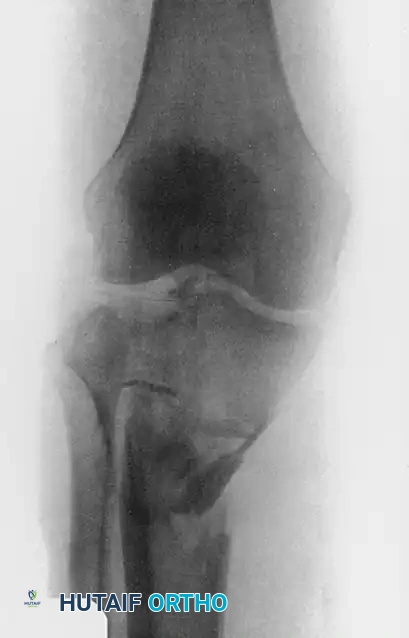

The evaluation of a patient with a suspected tibial plateau fracture demands a systematic, highly disciplined approach. A thorough history must be obtained, focusing on the mechanism of injury—typically an axial load combined with varus or valgus stress—as well as the patient’s overall medical status, physiological age, and functional and economic demands. High-energy trauma (e.g., motor vehicle collisions, falls from height) often results in complex, bicondylar fracture patterns with severe soft tissue compromise, whereas low-energy mechanisms in osteoporotic bone frequently produce isolated lateral depression fractures.

Vascular injuries, particularly to the popliteal artery, are highly associated with medial plateau (Schatzker IV) and bicondylar (Schatzker V and VI) fractures, as well as any fracture-dislocation variant. If clinical suspicion exists—indicated by diminished distal pulses, an Ankle-Brachial Index (ABI) less than 0.9, or asymmetric capillary refill—a CT angiogram or formal arteriogram must be obtained emergently. Patients with obvious vascular occlusion or transection require prompt transfer to the operating room for immediate vascular exploration, temporary skeletal stabilization (spanning external fixation), and revascularization.

Displaced fractures of the medial condyle (Schatzker IV) are high-energy, highly unstable injuries. They are best treated with open reduction and application of a medial buttress plate. Because the medial plateau bears approximately 60% of the knee's weight-bearing load, robust biomechanical support is mandatory.